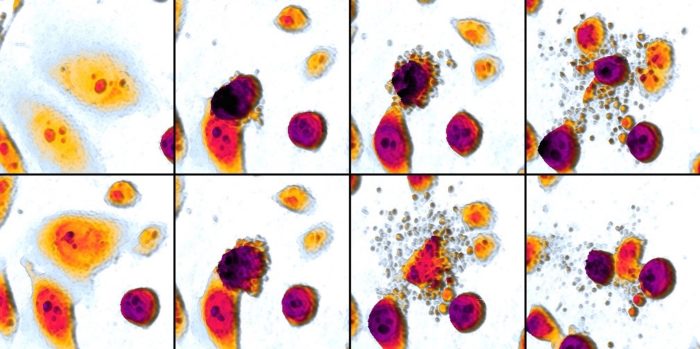

Lo studio, coordinato da Patrizia Limonta, si è concentrato sulle proprietà del delta‐tocotrienolo (δ‐TT) che si trova nell’olio di palma e nei semi di Annatto, utilizzati nell’America latina per la creazione di un colorante alimentare giallo-rossiccio. I benefici dell’olio di palma sono stati dimostrati con una serie di test. Ciò che è emerso dagli esami in vitro è la correlazione tra il δ‐TT e l’apoptosi, ovvero la morte cellulare programmata. Secondo i ricercatori milanesi e aquilani, attraverso un meccanismo detto “stress del reticolo endoplasmatico, il δ‐TT spingerebbe le cellule tumorali a un suicidio altruistico. Questo beneficio è stato confermato anche nei test in vivo. Infatti, il team ha potuto osservare il composto δ‐TT all’opera, constatando come sia capace di rallentare la crescita del melanoma e la progressione della malattia. Inoltre si è potuto dimostrare che il δ‐TT, nonostante le proprietà “aggressive” nei confronti delle cellule malate, non abbia alcun effetto negativo su quelle sane.